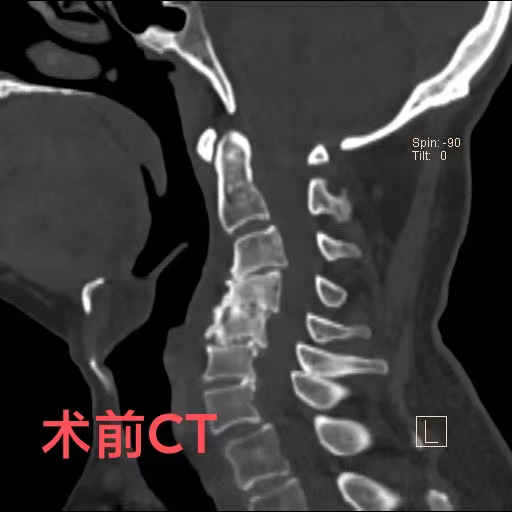

近日,74岁的陈爷爷,由于出现颈部疼痛、手脚麻木、行走困难等症状被家人送到重庆医科大学附属璧山医院(重庆市璧山区人民医院)康复医学科就诊。科室罗秋红主治医师为其进行了颈椎核磁共振检查,结果提示,患者颈椎变形已导致脊髓神经受压,随时有高位截瘫的风险。陈爷爷患有颈椎病多年,因担心手术带来的风险,长期依靠理疗来缓解病痛,这次也是因为症状日趋严重,无奈之下才前来就医。

罗医生第一时间联系了神经外科脊柱脊髓组的邓雷主治医师。针对陈爷爷及其家属的担忧,邓雷主治医师进行了耐心细致的沟通,最终陈爷爷决定配合医护进行手术治疗。患者高龄且有基础疾病,手术方案需要慎之又慎。神经外科副主任(主持工作)徐忠烨主任医师组织全科医生根据患者具体病情,制定了最终方案:前路3节段颈椎间盘切除+颈椎后凸畸形矫正。

陈爷爷长期的颈椎变形产生了大量骨质增生,给术中的邓雷、蒋登志医生出了难题。在神经显微镜下,他们的眼睛如鹰,指尖之中飞舞最温柔的神经刀锋,雕塑着最坚硬的颈椎骜骨。最终,手术耗时两个半小时,成功矫正,没有神经损伤!患者术后3天康复出院。